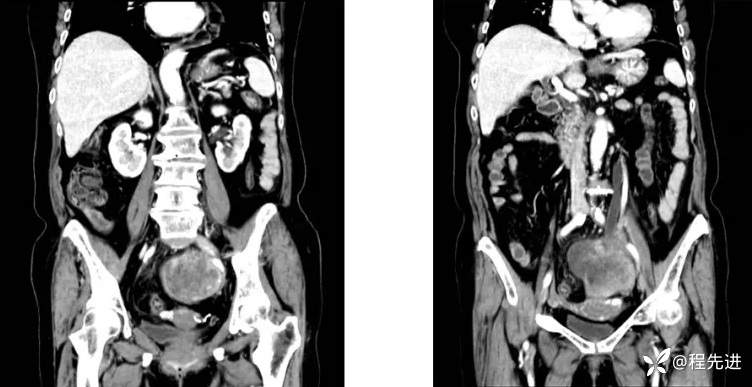

4月后患者再次腹痛半月来诊

CT平扫+增强:

既往史:腹膜后占位性病变切除术后、胆囊结石并慢性胆囊炎、高血压、高脂血症、癫痫。